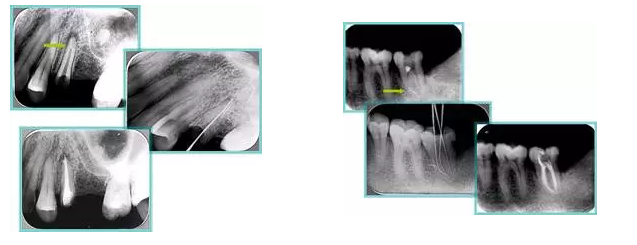

6. 鈣化

常見有修復(fù)性鈣化和增齡性鈣化。下面為根管鈣化 X 線片。

解決方法: ( 1 )清楚根管系統(tǒng)解剖形態(tài)。 ( 2 )安全頭的金剛砂鉆開髓,低速球鉆磨除鈣化牙本( ET20 ,ET40 ,DG-16 )。 ( 3 )徹底去除髓腔周壁的牙本質(zhì)齡。 ( 4 )借助化學(xué)性藥劑,如EDTA 等。

( 5 )初銼選用 8# 或 10#K 銼,平衡力法探察到工作長度 , H銼上下提拉法使根管擴(kuò)大,提高工作效率

7. 器械折斷

右圖及下圖為器械折斷的 X 線片。箭頭處示折斷器械。

解決方法: ( 1 )取出。 ( 2 )通過。 ( 3 )重新確定工作長度,充填。 ( 4 )根尖手術(shù)。

器械折斷可以不用取出,取出的原因多是患者心理因素。留在里面的器械關(guān)鍵是進(jìn)行消毒,預(yù)防性使用抗感染藥物,預(yù)防感染。